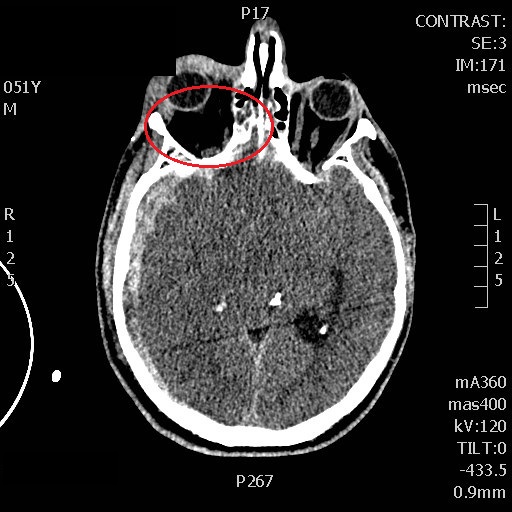

A 50 year old man was brought in by EMS after a 4 meter fall. He had isolated TBI and presented with a glascow of 5 (decorticating). An obvious right temporal deformity and a right fixed mydriasis were noted in the primary survey. My initial thoughts in the context of TBI was ongoing uncal engagement…a poor prognosis sign to say the least. However I noticed in the secondary survey a significant right periorbital ecchymosis with what seems to be a stint of exophtalmia. Was the bleeding solely preseptal, or could a retrobulbar hematoma explains the mydriasis? I reached for the ultrasound while anesthesia was intubating and was able to visualise black hypoechoic fluid in the retroorbital area. I promptly proceded to do a lateral canthotomy and a few minutes later both pupils were equal and reactive! This completly changed the momentum of the rescucitation since we were now looking at a patient with a much better prognosis then an actively herniating one! POCUS also resulted in a much shorter occular ischemia time since there would have been a significant delay if discovered only by the radiologist on CT scan.

Also, I was able to record a baseline internal carotid doppler waveform in the first minutes of rescucitation showing a markedly reduced diastolic flow (wasn’t able to find a vessel by TCD). I subsequently noticed improvement of the waveform following administration of mannitol which prompted me to be more agressive on the hyperosmolar therapy (started an hypertonic saline drip) despite the absence of clinical improvement at that time. In the next few hours, the patient waveforms further improved and the patient started withdrawing to pain.